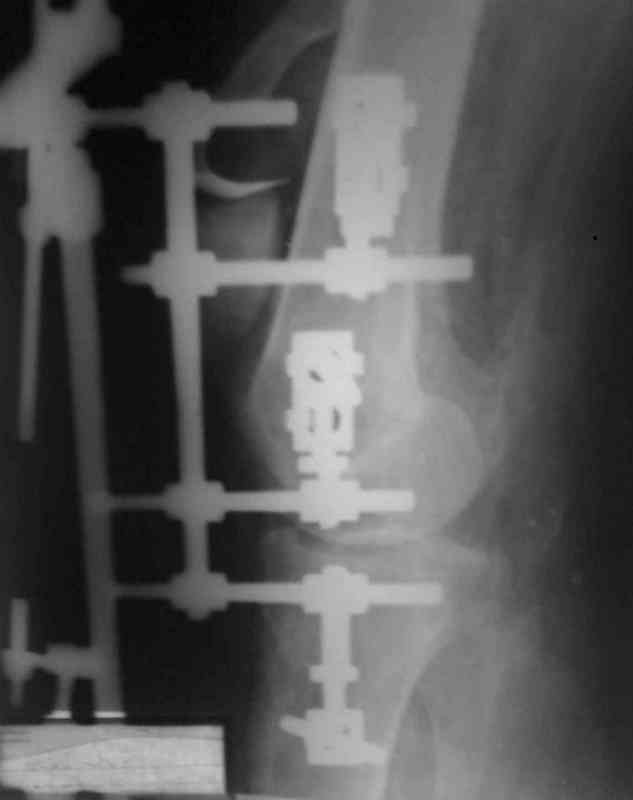

Bolnoi 27 let, DTP, Motorcycle trauma, postupil v kreane tiajelom sostoianii, osnovnia trauma- otkrity totalny vivih levogo kolennogo sustava s povrezdeniem malogo bersovogo nerva, tracionnoi povrezdenia podkolennoi arterii bez narushenia selostnost' sosuda, pomosh' okazanno v nujnum obmeme, kakoe ze mnenie uvazaemih kolleg naschet dalneshego vvedenia bolnogo? Castro

Uvajaemiy kollega! *Pomosh okazano v nujnom ob`eme*- kak ponyat? Vosstanovili krestoobraznih i bokovih svyazok? ili prosto vivih vpravili i fiksirovali AVF. sudya po R-snimkam nadkolennik nahoditsya visoko- znachit povrejdena i sobstvennaya svyazka, kotoraya ne ushita. Potom mojno sostavit plan lecheniya. S uvajeniem Abdurashid.

Доктор Castro,

На ренгенограмме хорошая аппозиция костей коленного сустава, но надколенник находится подозрительно высоко, поэтому необходимо убедиться в отсутствии повреждения связки надколенника.

Аппарат внешней фиксации удаляется в 6-7 недель,

предпочтительно под общим обезболиванием, во время

удаления проверяется стабильность и амплитуда движения в коленном суставе с редрессацией.

При пользовании стержневых наружных фиксаторов,

надо придерживаться правила проведения стержней подальше от зоны, на бедре лучше накладывать стержни косо передне-латерально, между брюшками прямой и vastus lateralis, а на голени по передне-медиальной поверхности большеберцовой кости, где отсутствует мышцы, иначе

восстановление движения в суставе тяжелее из-за

прошитых мышц спицами или стержнями аппарата.

Снимки прошлых публикации из моего Power point